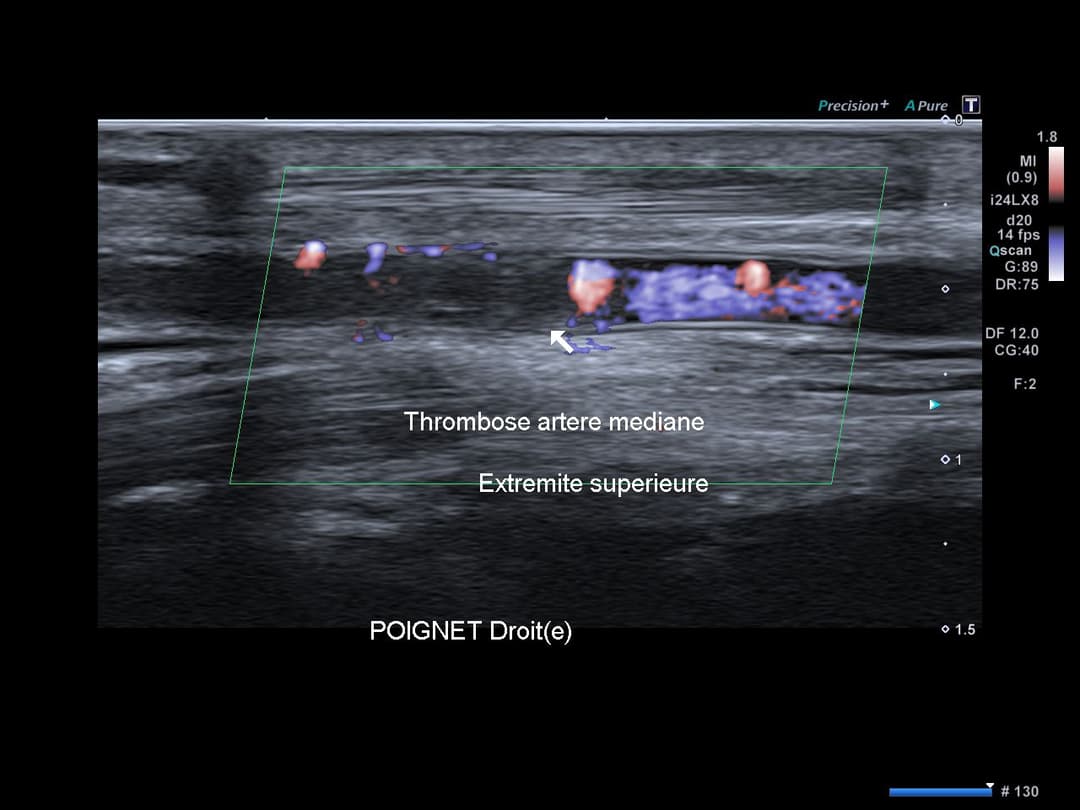

Matériel échogène endoluminale de l'artère médiane persistante du poignet droit, au niveau de son passage dans le canal carpien, traduisant une thrombose artérielle.

Accentuation de l'échogénicité des parties molles adjacentes traduisant un œdème réactionnel avec hyperhémie en Doppler couleur.